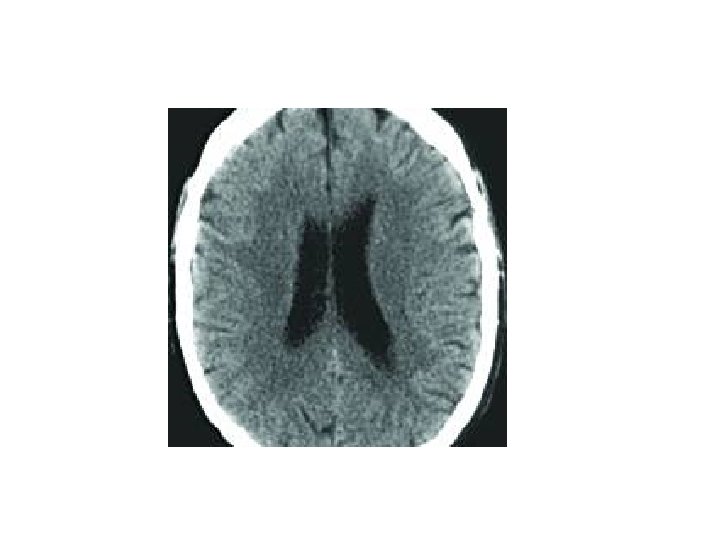

Diagnostic Tests • Diagnosis by ruling out other conditions including depression, hypothyroidism, infection, stroke • EEG shows slow pattern in later stages of disease • MRI and CT scan: shrinkage of hippocampus • Positron emission tomography (PET): visualizes brain activity and interactions • Folstein Mini-Mental Status: instrument reflecting loss of memory and cognitive skills

The scan below is a slice through the human brain and you should imagine that you are viewing it as if looking up from the patient's feet. Therefore, the patient's left is to the right of the screen. The shape of the ventricles is quite distinctive and they are shown outlined in green and orange. The presence of the third ventricle in the midline is one of the first things to look for. If the third ventricle is either not visible, or shows signs of shift away from the midline, this suggests that there is an abnormality. The basal cisterns is the fluid filled space around the back of the midbrain outlined here in purple. Blood clots, or swelling of the brain may cause this to become narrowed, or not visible altogether. Note in this scan, that the frontal horns of the lateral ventricles are symmetrical, with the septum between them in the midline.